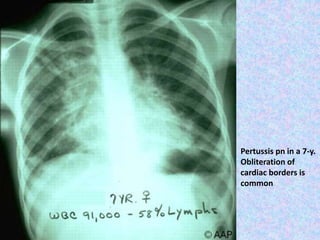

Pertussis pn in a 7-y.

Obliteration of

cardiac borders is

common